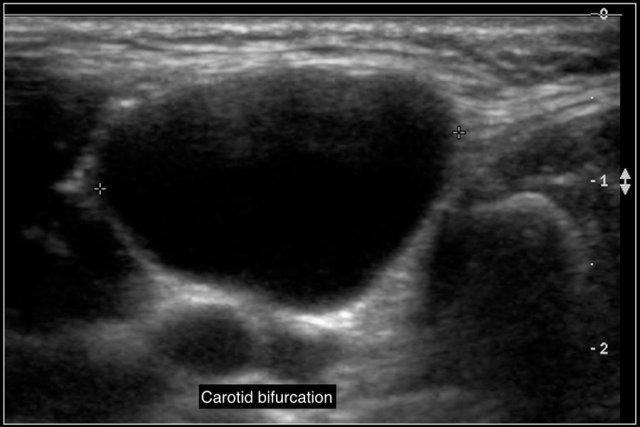

Đây là một nang khe mang khác với vị trí điển hình nằm nông so với chỗ phân đôi động mạch cảnh.